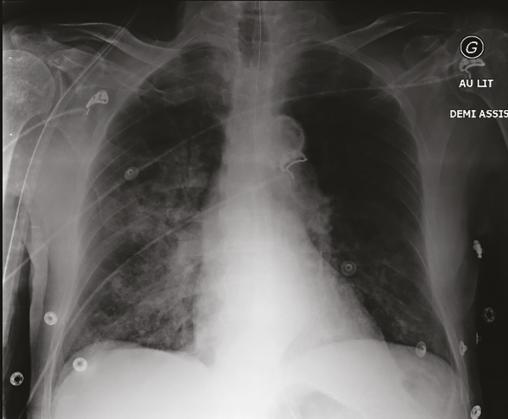

Cet homme de 94 ans, dément et hypertendu dans son Ehpad, était pris en charge par le SMUR pour une détresse respiratoire. Il était constipé depuis 1 semaine, avec des vomissements compliqués d’inhalation. Il avait une saturation en O2 à 50 % en air ambiant, remontée à 70 % sous masque à haute concentration. L’auscultation notait des ronchus et un foyer de crépitants à droite. Dans des matières fécales restées sur le sol se trouvait un long filament jaune (fig. 1 ). La prise en charge initiale consistait en une oxygénation haut débit, une aspiration pharyngée, une antibiothérapie par amoxicilline-acide clavulanique. La radiographie pulmonaire montrait une pneumopathie d’inhalation (fig. 2 ) avec détresse respiratoire dans un contexte de parasitose digestive, responsable d’un syndrome subocclusif. Dans le respect de ses directives anticipées, le patient était hospitalisé en soins palliatifs pour la suite de la prise en charge.